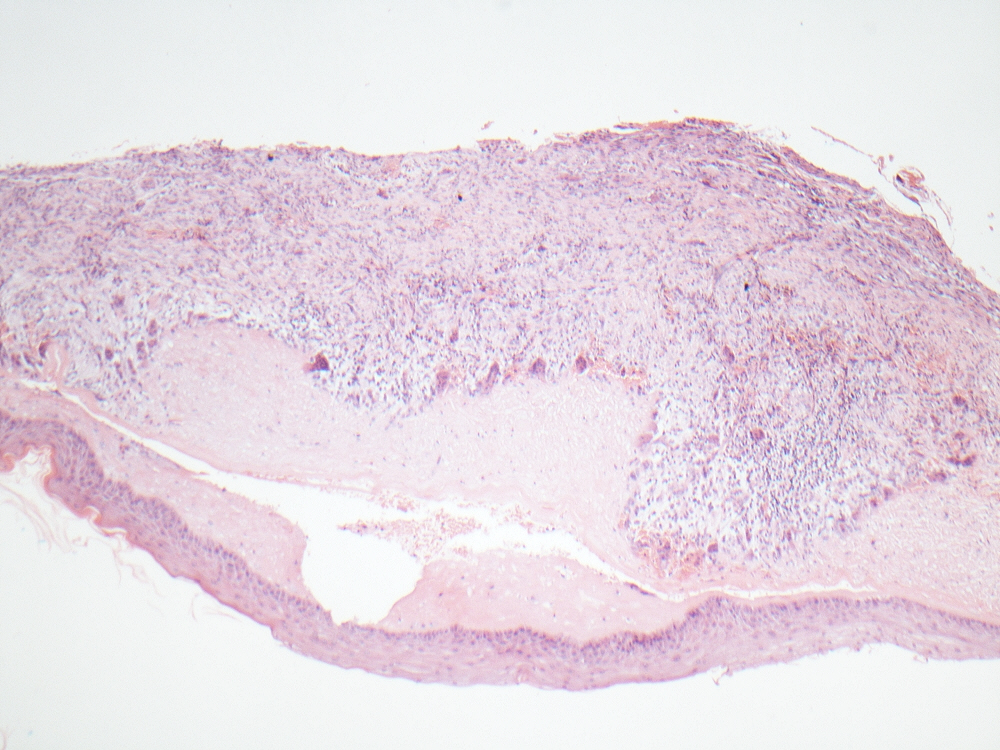

Recurrent odontogenic keratocyst with a zone of prominent subepithelial hyalinization being nibbled by hungry osteoclasts. Changes in the wall are almost giant cell granuloma-like. almost.... #oralpath #pathology